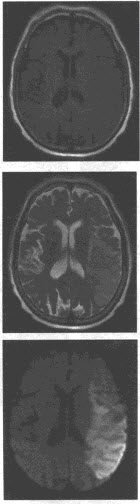

女性,9岁,头痛1周,肢体无明显障碍、MRI平扫T

2

WI及增强扫描如图,最可能的诊断为()

A:脑出血

B:胶质瘤

C:海绵状血管瘤

D:髓母细胞瘤

E:室管膜瘤